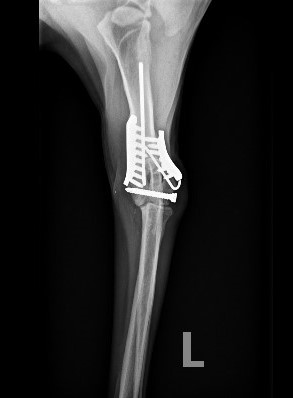

ADVANCED VETERINARY ORTHOPEDIC SERVICES

Our world-class, board-certified veterinary surgeons are dedicated to providing the most advanced canine orthopedic veterinary surgery and musculoskeletal assessment to ensure your beloved pet receives the most appropriate and comprehensive veterinary treatment available.